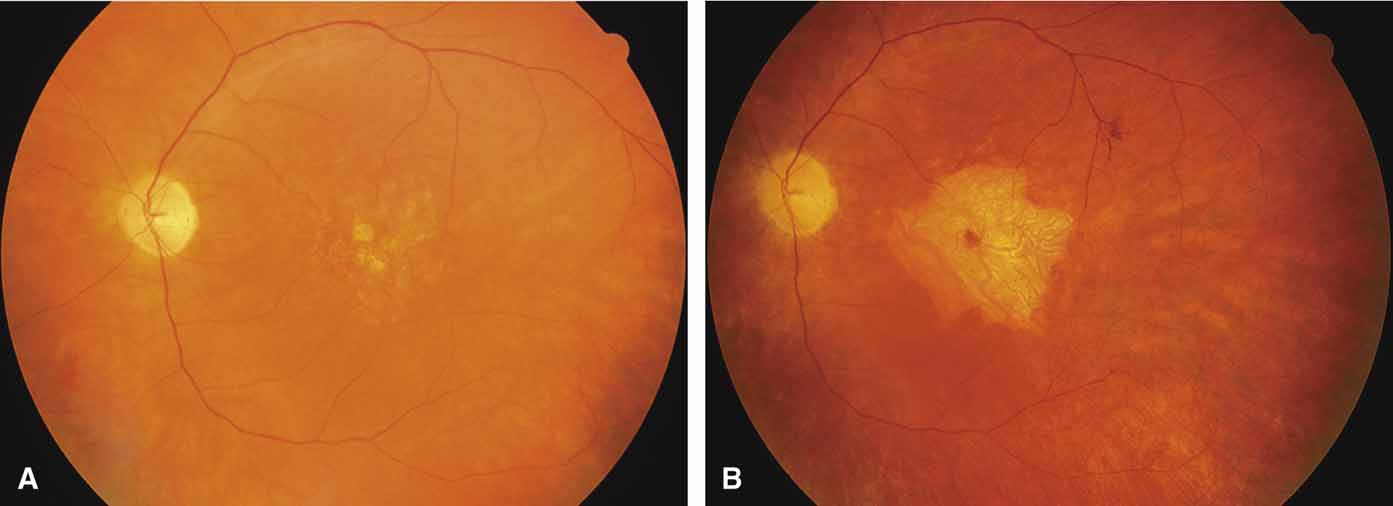

Serpiginous choroidopathy, also called serpiginous choroiditis, is a recurrent, progressive, destructive chronic degeneration of the choroid and retinal pigment epithelium that begins around the optic nerve and extends through the posterior pole.44 Unfortunately, some cases of this disorder have been reported under the name geographic helicoid peripapillary choroidopathy, and this has led to confusion with the clearly dominantly inherited genetic disorder first described in Iceland by Sveinsson26 in 1939 as choroiditis areata and subsequently renamed helicoidal peripapillary chorioretinal degeneration.27,28 The etiology of serpiginous choroidopathy is unknown, but the disease is not thought to be genetic. The disease starts as a gray, cream, or greenish discoloration and edema of the retinal pigment epithelium, followed by extension of the lesion, usually away from the disc, in a stepwise fashion (Figs. 8A and 8B). Vitritis is present in one-third of cases. Periods of quiescence or activity can be separated by months to years. Subretinal fibrous scarring, atrophy of the choroid, and hyperpigmentation in adjacent tissues can be prominent features (Figs. 8C and 8D). The prognosis for retention of central vision is poor because the disease process will often involve the macula. Systemic immunosuppression may be effective in prolonging remission and improving the visual outcome.45